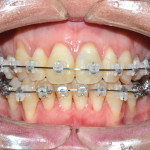

Corticotomie a scopo ortodontico: protocolli clinici e revisione della letteratura

Riassunto

L’intervento di corticotomia dento-alveolare è una metodica chirurgica consolidata, considerata una valida opzione terapeutica nel trattamento ortodontico del paziente adulto. Il meccanismo d’azione alla...